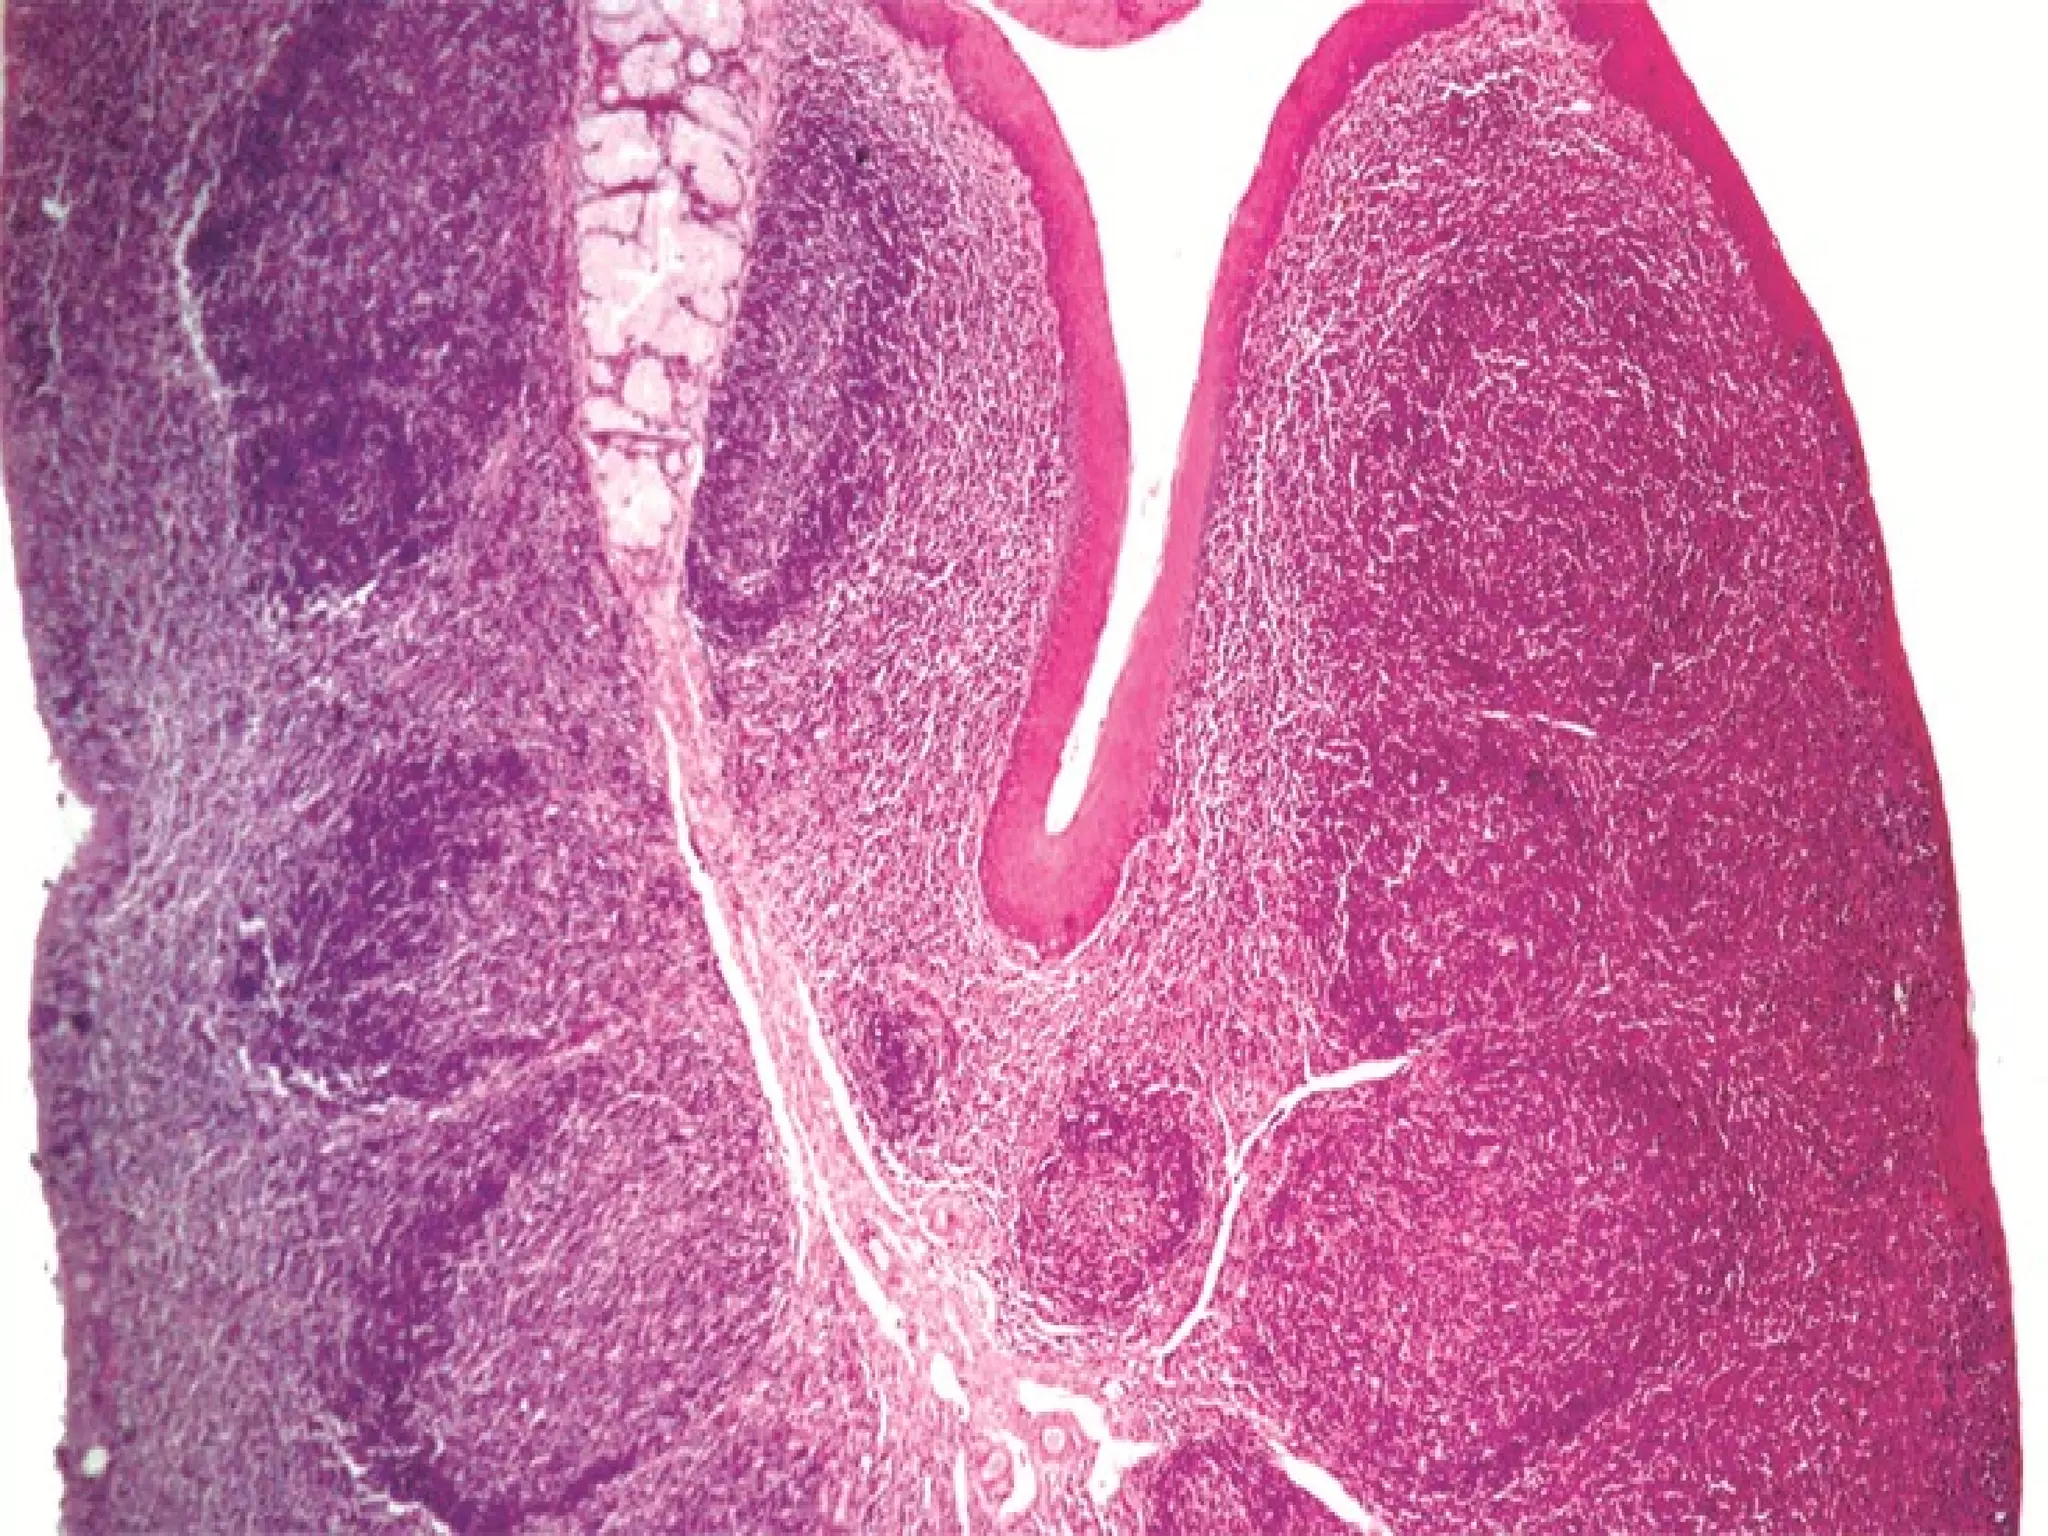

This document outlines several human body systems including the vascular, lymphatic, respiratory, digestive, and endocrine systems. It describes the trachea and lungs in the respiratory system, the oral cavity and digestive glands in the digestive system, and mentions the parotid, pancreas, and classic hepatic lobule in relation to the digestive system and endocrine glands.